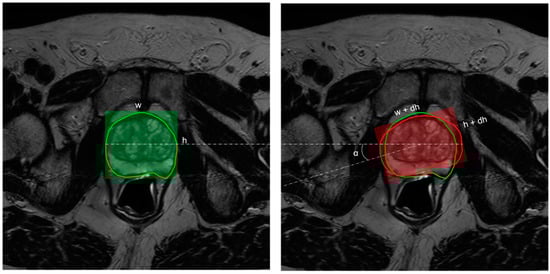

Figure 2.

Illustration of in-plane augmentation. The width, w, and height, h, associated with the contour drawn by the radiologist (left in green) in the axial plane are allowed to undergo random perturbation by a delta value—dw, dh ~ U (−2.7 mm, 2.7 mm). This results in a transformed contour (right in red) with width, w’ = w + dw, and height, h’ = h + dh. In addition to this, the contour is also allowed to randomly rotate in the z-axis at an angle, α ~ U(−5°, +5°).

As the name suggests, in-plane augmentation essentially simulates the variability in contouring within the axial plane (i.e., variations within X and Y dimensions associated with a slice). Here the prostate contours are allowed to have variations in their latero-lateral or antero-posterior dimensions by a value randomly sampled from a uniform distribution within the interval [−2.7 mm, +2.7 mm]. In addition to this, the contour is randomly allowed to rotate around the z-axis at a small angle, α ~ U(−5°, +5°) (see Figure 2). The choice of intervals for contour variability [−2.7 mm, +2.7 mm] was established by following the results of studies on the inter-observer variability in prostate contouring using MRI [49,50]. These studies report an average standard deviation of 1.1 mm, corresponding to 2.7 mm at a 95% confidence interval.